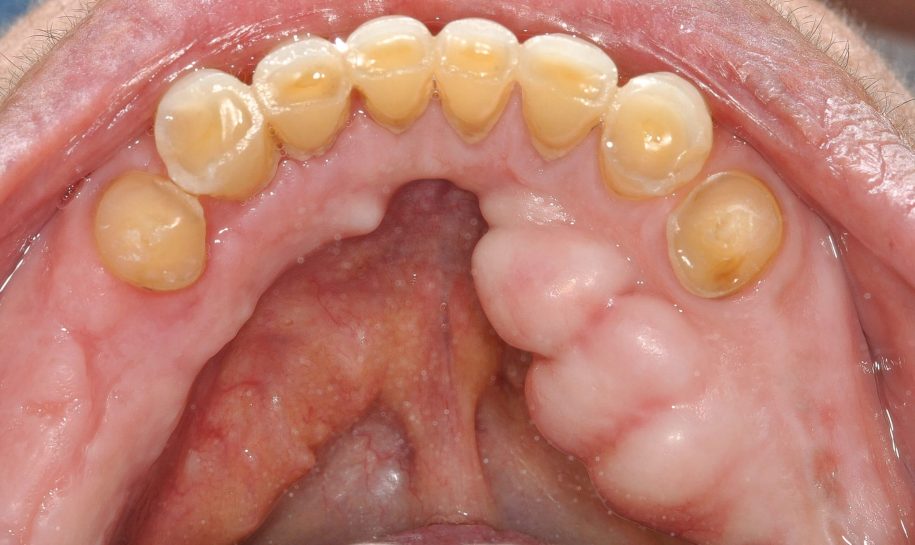

Torus mandibular. ¿Qué es y cómo tratarlo?

El torus mandibular es una protuberancia del hueso benigna que aparece con más frecuencia en la mandíbula. Crece con tanta lentitud que no causa síntomas, y con el paso de los años aumenta su tamaño.

Existen dos tipos de torus, el que aparece en la zona del paladar (torus maxilar), o el que aparece en la parte inferior de la boca (torus mandibular).